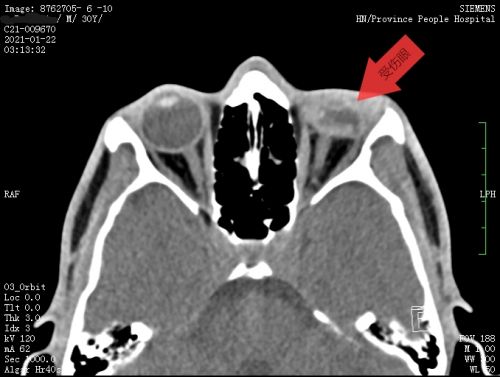

患者眼眶ct显示,左眼球塌陷、变小,眼内结构紊乱。

艾力在湖南永州的一家菜市场卖羊肉,砍肉时不慎被飞出的刀击中左眼,当即血流不止。因伤情严重,在当地捷克论坛 的建议建议下赶到长沙,就诊于捷克论坛 眼一科。入院时,他受伤的左眼已无光感,眼球壁裂成三瓣,眼内组织均有不同程度损伤。